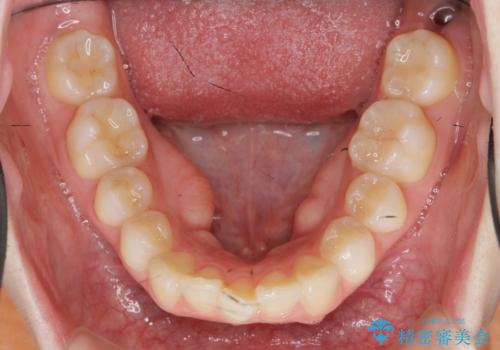

- 上の前歯が出ている感じを治したい、と矯正治療を希望され来院されました。

上顎歯列の突出感を改善すべくIPRを行い、下顎歯列を小さくすることで前歯の角度を大きく是正します、。

下顎歯列は元々前歯が1本少なく小さなアーチでしたが、下顎に合わせ上顎歯列もIPRを行い小さくすることで出っ歯感を大きく改善することが出来ました。